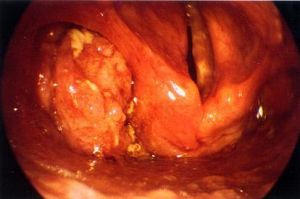

口咽癌根據發病部位不同,可分為舌根癌、舌咽齶弓(咽柱)癌、扁桃體癌及軟齶癌。不同部位的口咽癌臨床表現上存在著某些不同的部位特徵,但其主要臨床表現基本相似。有潰瘍型、外生型及侵潤型3種。口咽癌初期症狀不明顯,可有咽部分不適、異物感。腫瘤破潰感染後出現咽痛,固定於病變側,也可有舌咽神經反射的耳內推。如腫瘤在扁桃體咽側壁,向深侵及鼻咽部,可造成一側耳悶、聽力減退。如腫瘤侵及咽側、侵犯翼內肌,可出現張口困難。舌根部腫瘤向深部侵潤後,可出現深舌偏斜和發音障礙,且常有唾液帶血、口臭、呼吸不暢等。腫瘤長大,因阻塞可產生呼吸及吞咽困難。

口交會引起口咽癌(2)漬瘍:口咽部鱗癌易發生潰瘍,多為質硬,邊緣隆起不規則、基底呈凹凸不平的浸潤腫塊,潰瘍面波及整個腫瘤區。

舌根癌可見舌根部一側隆起,舌會厭奚谷被腫塊填滿;會厭癌於間接喉鏡下可見會厭軟骨如菜花狀胂潰。